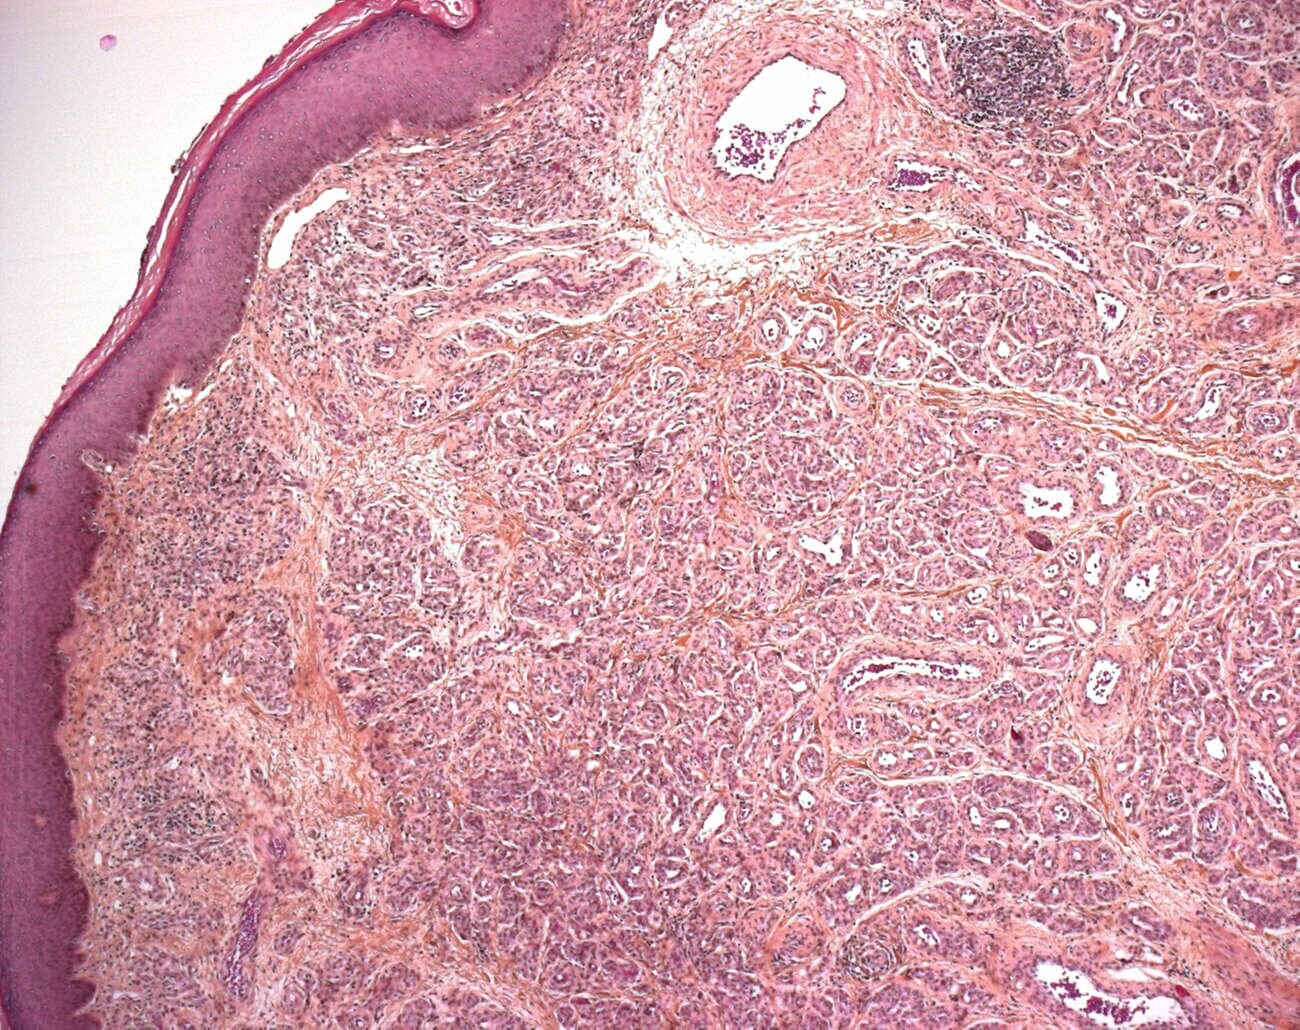

These tumors are highly cellular, involving the dermis, often with extension into the subcutis. The tumor has a lobular architecture and plump endothelial cells. The latter cells express glut-1 antigens throughout the life of this tumor.

lobular architecture

proliferative phase